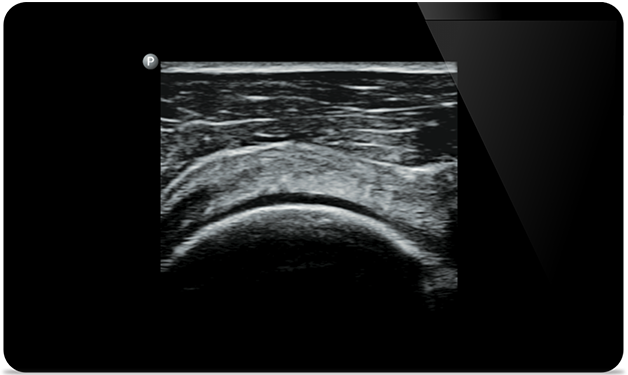

O Lumify ajuda você a ver os detalhes finos em músculos, articulações, ligamentos, tendões e cartilagem para fazer um diagnóstico mais preciso de lesões.

O Lumify pode ajudar a avaliar pacientes da cabeça aos pés, seja fascite plantar, tendinite ou bursite no tendão patelar, ou mesmo instabilidade do ombro no manguito rotador.

A SonoCT reforça o diagnóstico por imagem real do tecido enquanto elimina artefatos aleatórios. Essa tecnologia produz diagnóstico por imagem superior aos convencionais em até 94% dos pacientes.